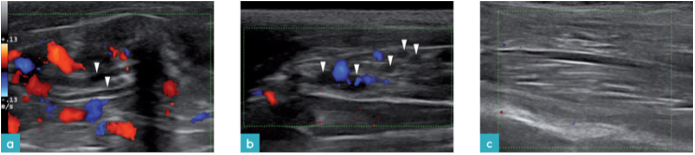

血管的超声影像为管状结构,由高回声外壁和无回声的内腔组成。浅表血管,尤其是静脉,易被探头所施的外力压塌。因此建议扫查这类血管时轻压即可。彩色多普勒或脉冲多普勒可用于区分浅表血管与其他结构。

神经的超声影像表现为低回声管状结构。神经的矢状面上可见两条高回声亮线,横截面则呈现为高回声亮线包围低回声组织形成的椭圆形或圆形结构(图10)。